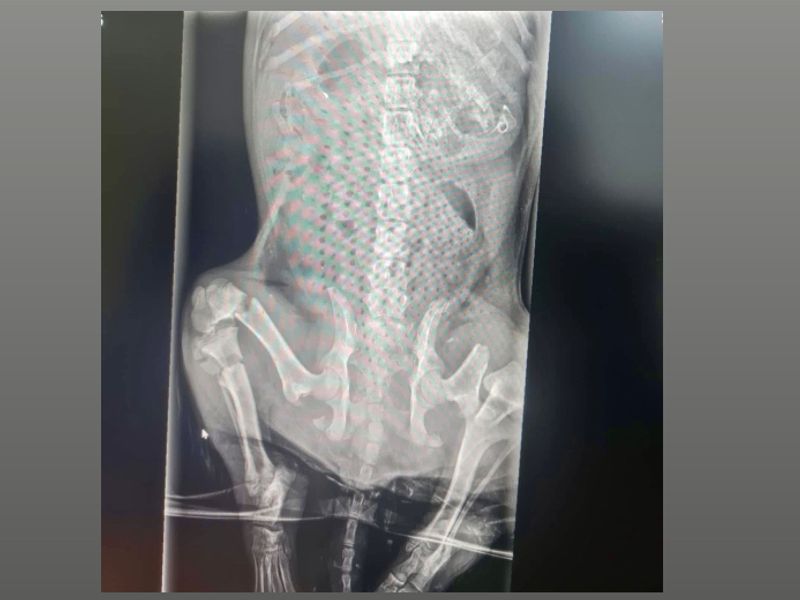

Dit kleine reutje heeft een heel triest verleden achter zich .......... In februari 2025 werd een rescue dame gebeld door de politie ong. 40 km vanaf Craiova. Er was een pup overreden en zat vast in een gracht in bevroren modder ............. Toen zij hem ging halen om naar de dierenarts te brengen schreeuwde hij het uit van de pijn .......... Hij had 4 breuken en is geopereerd. Hij heeft zo hard gevochten, dit kleine mopje en nu is hij als herboren. Alles perfect genezen ! Niettegenstaande zijn verleden is Simon een geweldig lieve vriendelijke schat en kan met alles en iedereen. Wil jij Simon zijn gouden forever home geven, neem dan snel contact met ons op !